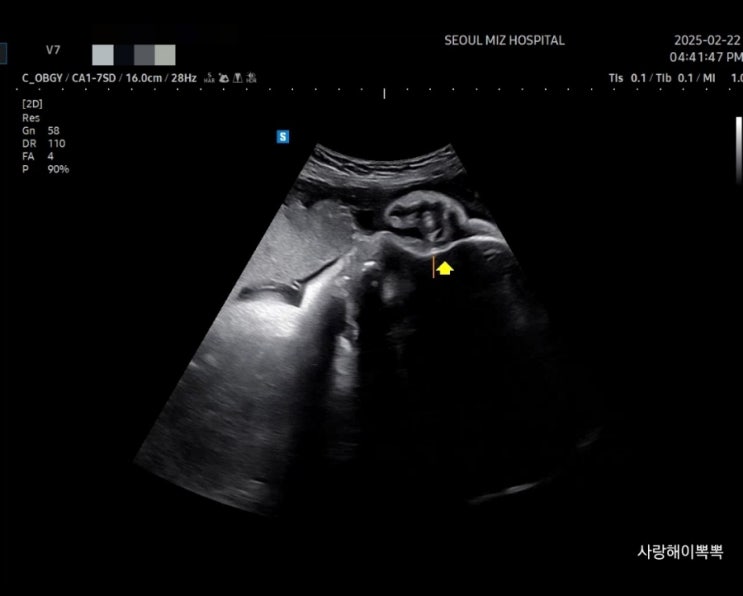

서울미즈병원 자연분만 실패 응급제왕 수술 후기 /아빠와 목욕수업 / 모유수유실 / 밥 후기

서울미즈병원 자연분만 실패 응급 제왕 수술 일요일 아침 진통 시작으로 병원 응급분만실 방문 하필 일요일...

[38주차]미즈 문화센터 딸기축제 많이 걷기

https://m.blog.naver.com/dlstudl/223767107570 1. 미즈 문화센터 - 모유수유 특강 모유수유 벼락치기 공...